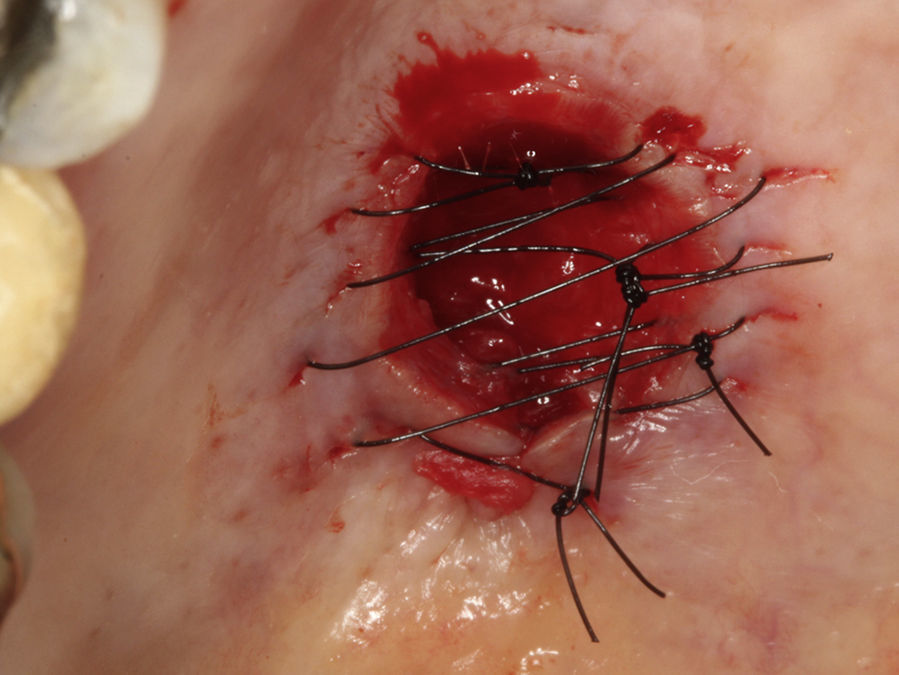

Casos clínicosCaso 1Paciente do sexo masculino, 68 anos de idade, leucoderma, procurou a Clínica de Estomatologia do Departamento de Odontologia da Pontifícia Universidade Católica de Minas Gerais (PUC Minas) queixando‐se de aumento de volume no palato, com tempo de evolução de 2 anos e discreta sintomatologia dolorosa. A anamnese não revelou alterações sistémicas. Ao exame clínico extraoral não foram observadas alterações. O exame clínico intraoral mostrou lesão nodular, pediculada, de consistência firme, localizada no palato duro do lado direito, entre os pré‐molares superiores e a rafe palatina, medindo aproximadamente 2cm na sua maior extensão. Foi realizada uma radiografia oclusal de maxila que não mostrou alterações ósseas. As hipóteses diagnósticas de neoplasia de glândula salivar e neoplasia mesenquimal benigna foram consideradas. Foi realizada biópsia incisional com diagnóstico anatomopatológico de adenoma pleomórfico. O tratamento proposto para a lesão foi a remoção cirúrgica conservadora. Paciente retornou após 4 semanas exibindo, ao exame intraoral, ulcerações na mucosa que recobria a lesão (fig. 1). Inicialmente, foi realizada anestesia local por meio da técnica supraperiosteal para bloqueio de ramos do nervo palatino maior, com cloridrato de lidocaína 2% e epinefrina 1:100.000 (ALPHACAINE 100®, DFL, Rio de Janeiro, Brasil). Em seguida, foi realizada incisão na base da lesão com bisturi lâmina 15 (Solidor, São Paulo, Brasil) e, após o descolamento do retalho mucoso palatino, a lesão foi exposta e removida (fig. 2). Foi realizada limpeza da ferida cirúrgica e sutura com fio seda Ethicon™ 4.0 (Johnson & Johnson, São Paulo, Brasil) (fig. 3). A lesão excisada (fig. 4) foi fixada em solução de formaldeído a 10% e enviada para exame anatomopatológico no Laboratório de Patologia Bucal da PUC Minas.

Paciente do sexo feminino, 31 anos de idade, leucoderma, foi encaminhada pelo cirurgião‐dentista à Clínica de Estomatologia do Departamento de Odontologia da PUC Minas para avaliação de lesão nodular no palato duro com diagnóstico histopatológico de adenoma pleomórfico, obtido por meio de biópsia incisional. Durante a anamnese, a paciente relatou a evolução da lesão há 4 anos com característica assintomática. Relatou estar no sexto mês de gestação e não apresentava outras alterações sistémicas. O exame extraoral mostrou ausência de alterações. Ao exame intraoral, observou‐se um aumento de volume bem delimitado no palato duro do lado direito, de consistência firme e coloração semelhante à da mucosa normal, medindo aproximadamente 2,5cm, exibindo pequena área de ulceração no local da realização da biópsia incisional (fig. 9). O exame radiográfico não mostrou alterações. O tratamento proposto foi a remoção cirúrgica conservadora e confecção de placa palatina em acrílico com grampos retentores para minimizar o desconforto pós‐operatório. Foi realizada anestesia local com lidocaína 2% e epinefrina 1:100.000 (ALPHACAINE 100®, DFL, Rio de Janeiro, Brasil), seguida de incisão semilunar com bisturi lâmina 15 (Solidor, São Paulo, Brasil) e rebatimento do retalho mucoso. Como a lesão se apresentava encapsulada, foi possível destacá‐la da mucosa suprajacente com facilidade (fig. 10). O retalho foi reposicionado por meio de pontos isolados (fig. 11) e a lesão (fig. 12) foi fixada em formaldeído a 10% para realização de exame anatomopatológico no Laboratório de Patologia Bucal da PUC Minas. Em seguida, foi colocada a placa de acrílico (fig. 13) para proteção da região operada e controlo da sintomatologia dolorosa.

No primeiro caso relatado, devido à remoção da lesão com toda a mucosa sobrejacente, a cicatrização ocorreu por segunda intenção e a sintomatologia dolorosa foi controlada com utilização de anti‐inflamatório e analgésico. No segundo caso, durante a exposição da lesão, foi verificada que a mesma se apresentava encapsulada, o que permitiu sua enucleação com preservação da mucosa e consequente cicatrização por primeira intenção. Como a lesão era extensa, previamente à cirurgia foi confeccionada a placa de acrílico que contribuiu para a ausência de dor pós‐operatória, aliada ao uso de medicação analgésica. Devido à impossibilidade de se determinar antes da cirurgia a relação da lesão com a mucosa sobrejacente e a possível necessidade de remoção desta mucosa, consideramos que a proteção do palato com um dispositivo de acrílico seja uma excelente opção para proteção e controle da dor pós‐operatória. O palato é uma área de contato direto com alimentos e, com a própria língua e a utilização de dispositivo móvel de proteção, pode contribuir também para o processo de cicatrização.